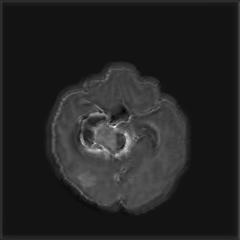

(a) (b) (c) (d)

Boundary Stream:

Fig. 2 demonstrates the output of each of the attention layers in our dedicated boundary stream. In essence, each attention layer progressively localizes the tumor and refines the boundaries. The first attention layer has learned rough estimate of the boundaries around the tumor and localized it, whereas the second and third layers have learned more fine-grained details of the edges and boundaries, refining the localization. Moreover, since our architecture leverages a dilated spatial pyramid pooling to merge the learned feature maps of the regular segmentation stream and the boundary stream, multiscale regional and boundary information have been preserved and fused properly, which has enabled our network to capture the small structural details of the tumor.